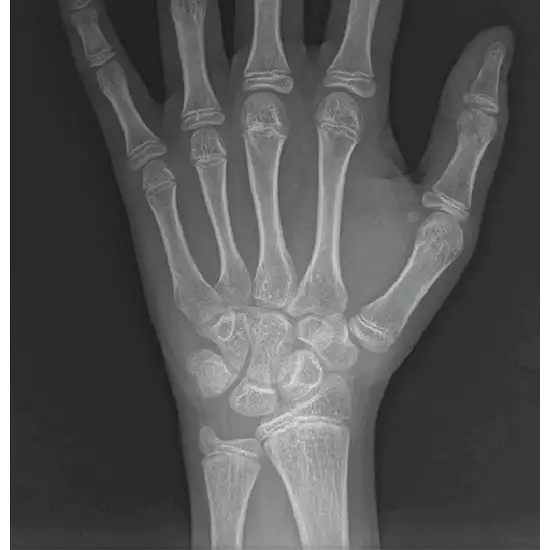

The results of bone age research provide medical professionals with a better idea of how mature a child's skeletal system is. A single X-ray is taken of the patient's left wrist, hand, and fingers to do this.